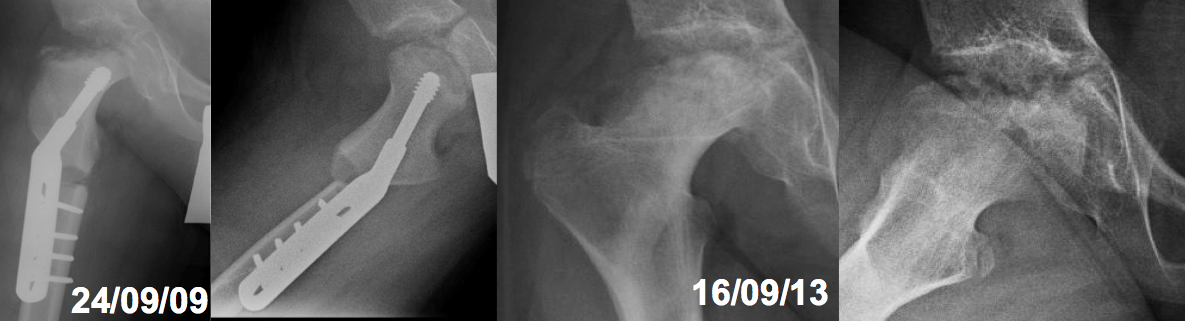

Enfermedad de Legg-Perthes-Calvé recurrente. Descripción de un caso y revisión de la literatura. [Recurrent Legg-Perthes-Calvé disease. A case report and literature review]